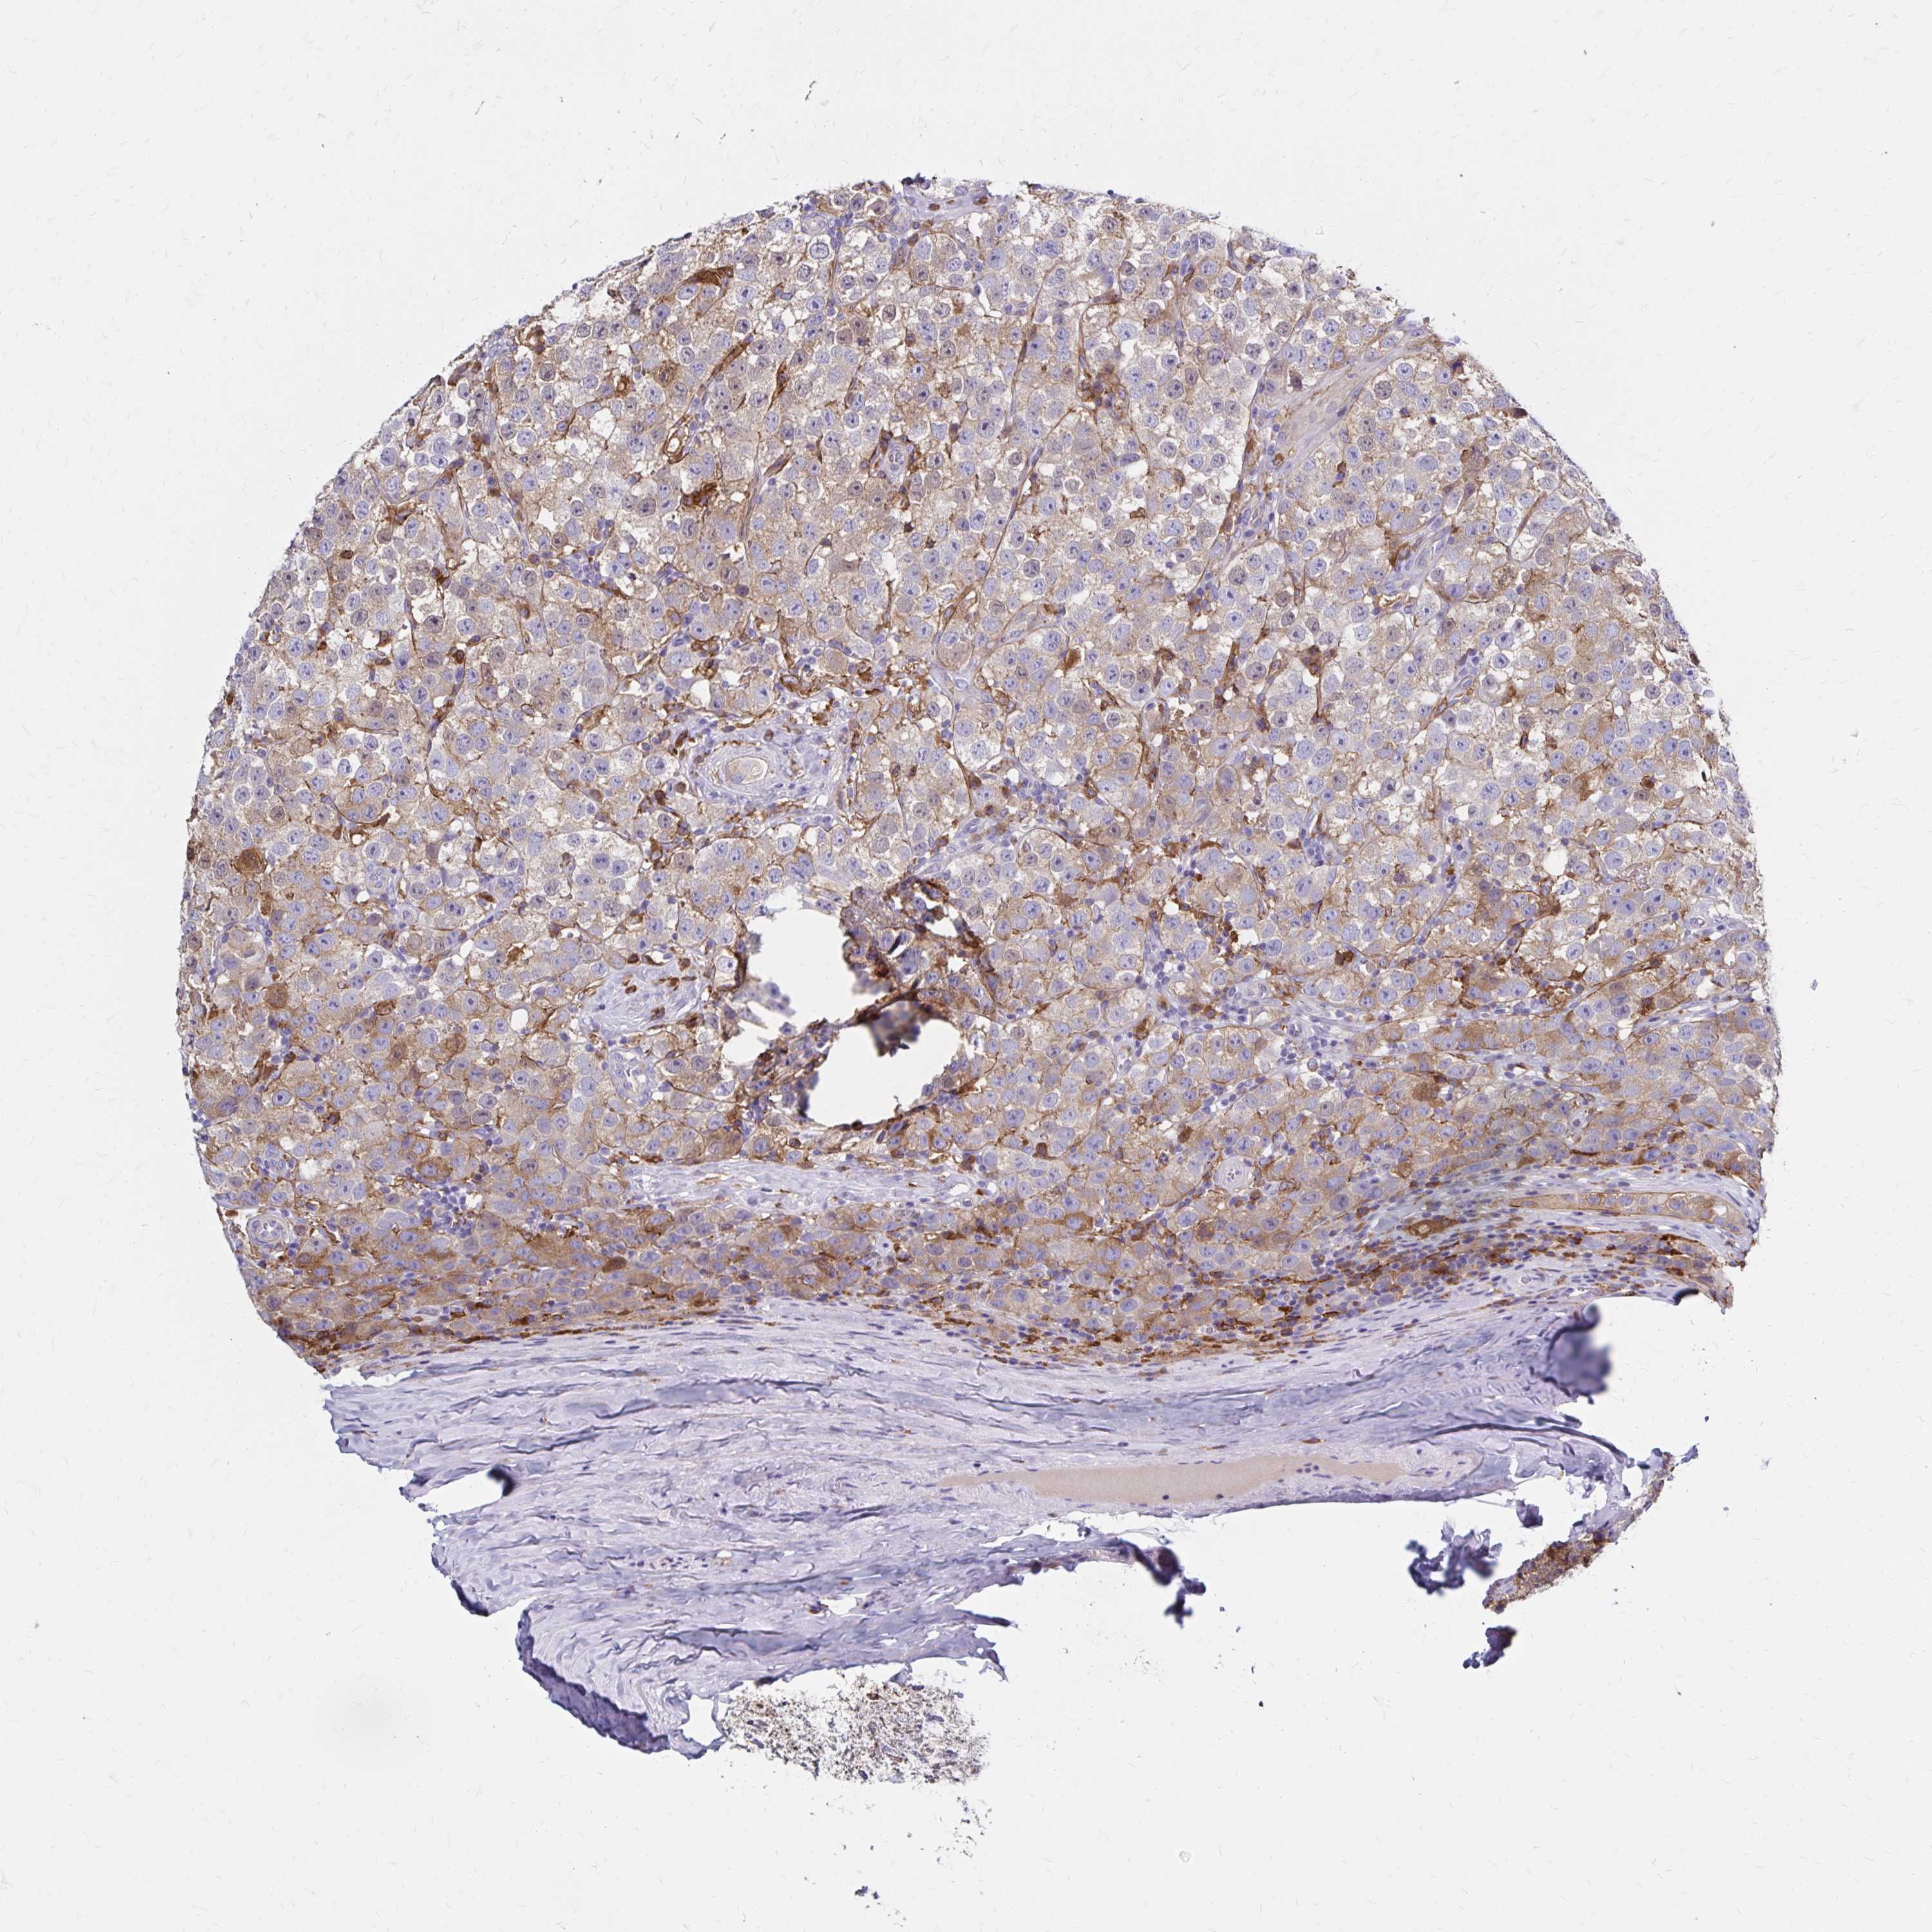

TESTIS CANCER - Protein expressioni

A mouse-over function shows sample information and annotation data. Click on an image to view it in a full screen mode. Samples can be filtered based on level of antibody staining by selecting one or several of the following categories: high, medium, low and not detected. The assay and annotation is described here.

Note that samples used for immunohistochemistry by the Human Protein Atlas do not correspond to samples in the TCGA dataset.

Antibody stainingi

Antibody staining in the annotated cell types in the current human tissue is reported as not detected, low, medium, or high, based on conventional immunohistochemistry profiling in selected tissues. This score is based on the combination of the staining intensity and fraction of stained cells.

Each image is clickable and will lead to virtual microscopy that enables deeper exploration of all samples and also displays staining intensity scores, fraction scores and subcellular localization as well as patient and tissue information for each sample.

Antibody HPA055338

Antibody HPA056015

Staining

High

Medium

Low

Not detected

Intensity

Strong

Moderate

Weak

Negative

Quantity

>75%

75%-25%

<25%

None

Location

Nuclear

Cytoplasmic/membranous

Cytoplasmic/membranous,nuclear

Seminoma, NOS